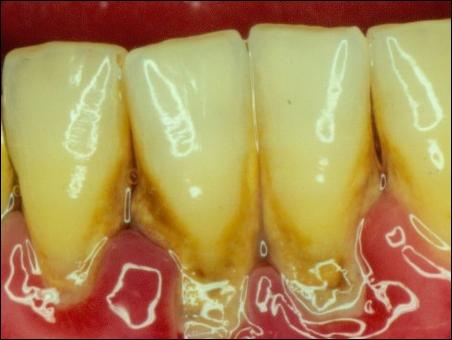

第二,是刷牙不好,尤其是下面的門牙,導致牙結石的滋生。

牙齒附著在牙槽骨上,外面包裹著牙齦。當牙周袋形成后,牙菌斑就會寄居于此,在牙菌斑細菌的作用下就會不斷地發(fā)炎,一方面它會侵蝕牙槽骨,讓牙槽骨慢慢地吸收;另一方面,牙齦腫脹發(fā)炎會降低牙齦與牙齒的附著力,兩種合力共同作用的結果,就是牙齒會越來越松動,直到失去固有的功能。